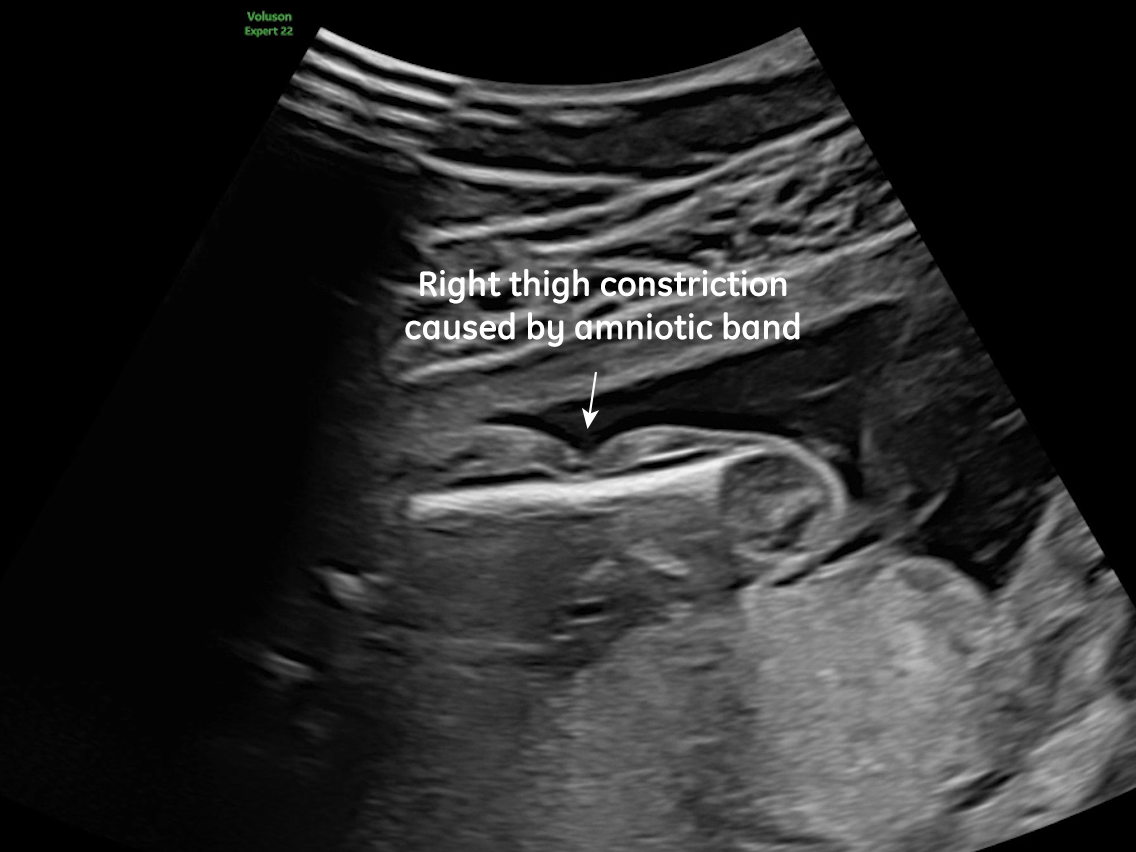

We present a case of Amniotic Band Sequence seen in 21st week of pregnancy. The fetus showed the following findings:

- Constriction of the right thigh by the amniotic band

Prenatal ultrasound imaging shows thin echogenic bands attaching to both the uterine wall and associated fetal structures. The bands themselves can be difficult to detect, hence the visualization of bands is not required to suggest the diagnosis. Random anomalies that do not follow a pattern should lead the clinician to suspect amniotic band sequence and prompt close evaluation for a causative band [5, 6]. The defects resulting from the bands are categorized into various categories: neural tube-like defects, craniofacial anomalies, limb anomalies, abdominal and thoracic wall defects, and visceral anomalies [7, 8]. The most common findings are those caused by constriction rings in the limbs, which are present in at least 80% of cases. They may vary in depth, involving only the skin, to involving bone and causing edema of the distal limb, extremity asymmetry, pseudosyndactyly, or amputation of limbs or digits [8]. Histologically, constriction bands are composed of fibrous tissue containing fibroblasts covered by squamous cells, which may make them inelastic and produce a ligature effect [9]. Clubfoot deformity of the lower extremity is found in up to one third of cases, probably secondary to the presence of oligohydramnios if there is loss of amniotic fluid [6].